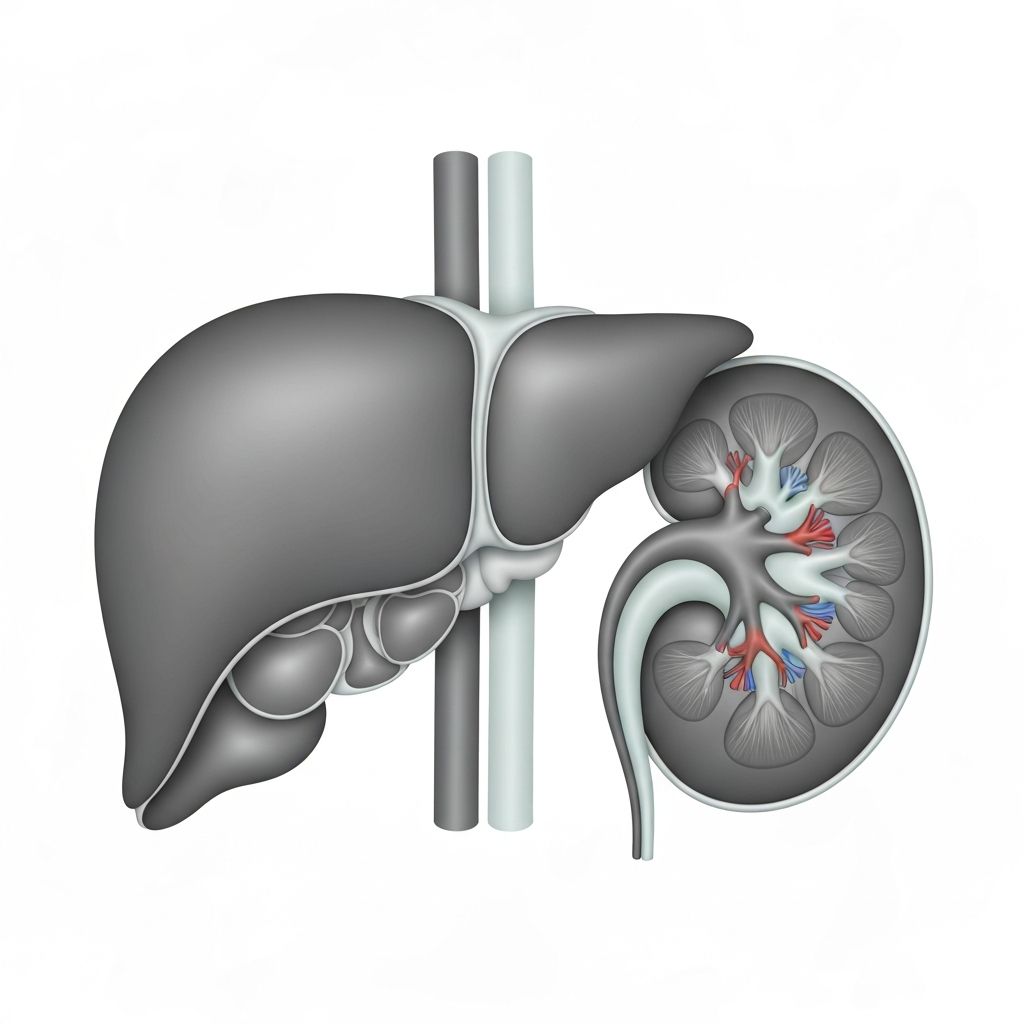

Primary Organs and Their Roles

The human body has evolved sophisticated systems to process and eliminate substances that cannot be used for energy or structural functions. These systems involve the liver, kidneys, lungs, skin, and gastrointestinal tract working in coordination.

Key Detoxification Organs

The liver is the primary organ responsible for metabolizing foreign compounds through enzymatic pathways. The kidneys filter metabolic waste from the bloodstream. The lungs eliminate volatile compounds through respiration. The skin has limited excretory function, primarily through sweat containing water-soluble compounds.